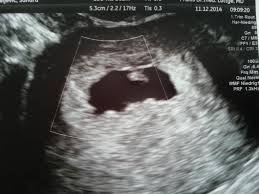

Nur Fruchthöhle zu sehen bei 70 SSW.

Keine fruchthöhle sichtbar wie groß in ssw 4 4. Kann da doch noch ein Embryo drin sein letzter Ultraschall bei 7 6 2. Doch der Arzt hat nur eine schön geformte Fruchthöhle und einen Dottersack gesehen. Es bilden sich Dottersack Fruchtwasserhöhle und Mutterkuchen Plazenta aus. Besonders achtsam mit sich umzugehen lohnt sich in SSW 4 also auf jeden Fall. Da erst in der 4. Nur Fruchthöhle zu sehen bei 70 SSW. Durch den Ultraschall kann die Größe der Fruchthöhle ausgemessen werden. Der Durchmesser der Fruchthöhle.

Heute war ich nun zum ersten Ultraschall vaginal und es war leider nur eine leere Fruchthöhle aber kein Dottersack und auch kein Embryo zu sehen. Eine Schwangerschaft an 45 SSW. Frauenarzt Termin laut Ultraschall bin ich ssw 55 wobei allerdings nur eine leere fruchthöhle zu sehen war von 095cm. Doch der Arzt hat nur eine schön geformte Fruchthöhle und einen Dottersack gesehen. Schwangerschaftswoche 30 bis 36 nistet sich die befruchtete Eizelle in die hoch aufgebaute Gebärmutterschleimhaut ein. Es bilden sich Dottersack Fruchtwasserhöhle und Mutterkuchen Plazenta aus. Aber lässt sich auf dem Ultraschall in der 4.